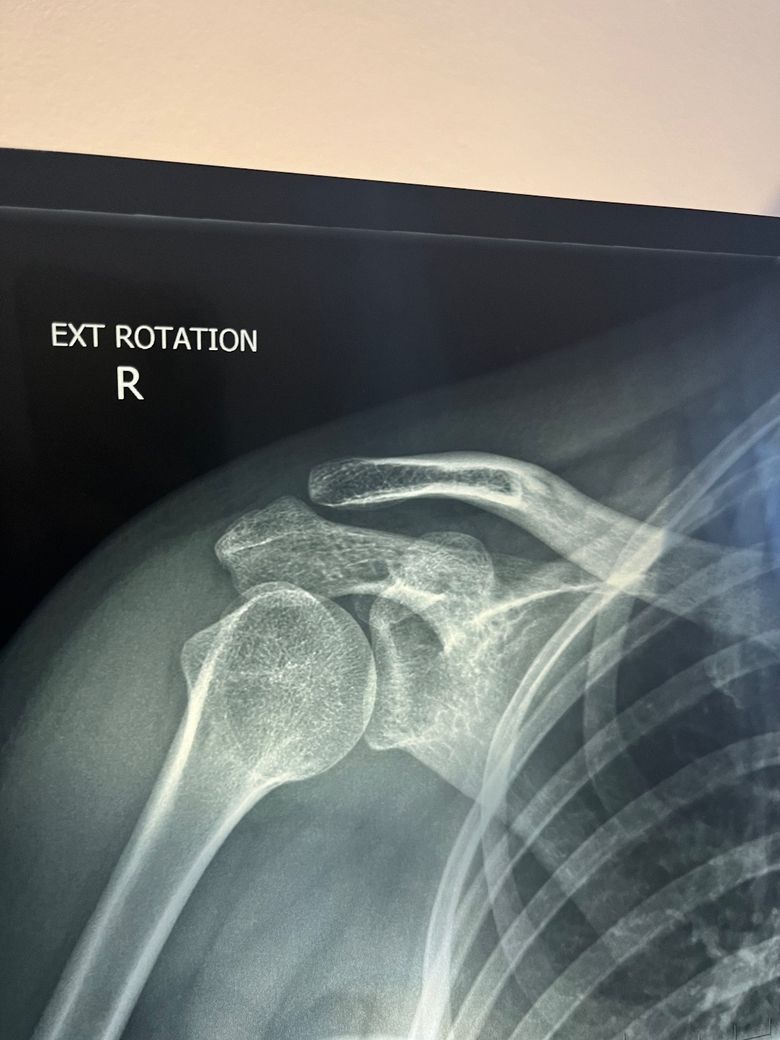

쇄골이 아픈데 엑스레이 상으로 짐작가시는 이유가 있을까요?

1월 말부터 오른쪽 쇄골이 아프기 시작했습니다. 지금은 초반보다는 통증이 덜하지만 여전히 쇄골쪽으로 무게가 가해지는 행동을 하면 다시 통증이 시작됩니다.

엑스레이와 씨티를 찍었더니 골절도 아니라고 하시는데 도대체 뭐가 문제일까요ㅠㅠ

CT Findings: A well-corticated linear oblique lucency through the right mid clavicle corresponds to a prominent nutrient foramen.

No clavicle fracture. Normal right-sided acromioclavicular and sternoclavicular joints.

Normal glenohumeral joint, proximal humerus and scapula.

The visualised chest and ribs are normal.

CT Conclusion: A well-corticated linear oblique lucency through the right mid clavicle corresponds to a prominent nutrient foramen.

• 2번 째 사진